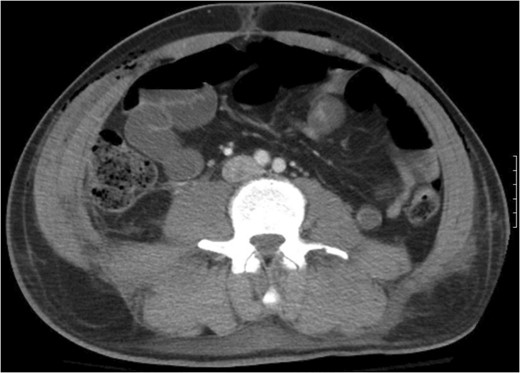

A 43-year-old male patient presented with a right-sided traumatic lumbar hernia after a blunt mechanism. The patient had been pinned between a dirt-mover’s claw arm resulting in a crush mechanism. He sustained injuries to the lumbar spine, sacrum, abdominal wall and 12th rib. On presentation, he did not have clinical or radiographic evidence necessitating abdominal exploration and was observed in a monitored setting. Computed tomography imaging demonstrated a Grynfeltt defect with herniation of the ascending colon and cecum through an area defined by the 12th rib, quadratus lumborum and internal oblique (Figures 1 and 2). After several days of observation and recuperation, the patient continued to have significant pain overlying the hernia site. We electively brought him to the operating room on post-injury Day 4. A laparoscopic repair of the traumatic hernia was performed. Key operative steps included: (i) Wide exposure of the hernia defect via incision of the peritoneum and transversalis as well as mobilization of the ascending colon and duodenal sweep (Figures 3 and 4). (ii) Primary repair of the defect with intra-corporeal suturing of the oblique musculature (Figures 5 and 6). (iii) Placement of an underlay mesh with appropriate redundancy at least 4 cm in all directions around the defect and seating against the iliac crest (Figure 7). Post-operative imaging demonstrates obliteration of the hernia defect and restoration of the abdominal wall (Figures 8 and 9). The patient has recovered, returned to the work force and has no pain or bulge at the repair site 6 months after injury.

The traumatic lumbar hernia is seen on the right side of the abdominal wall above the iliac crest on computed tomography.